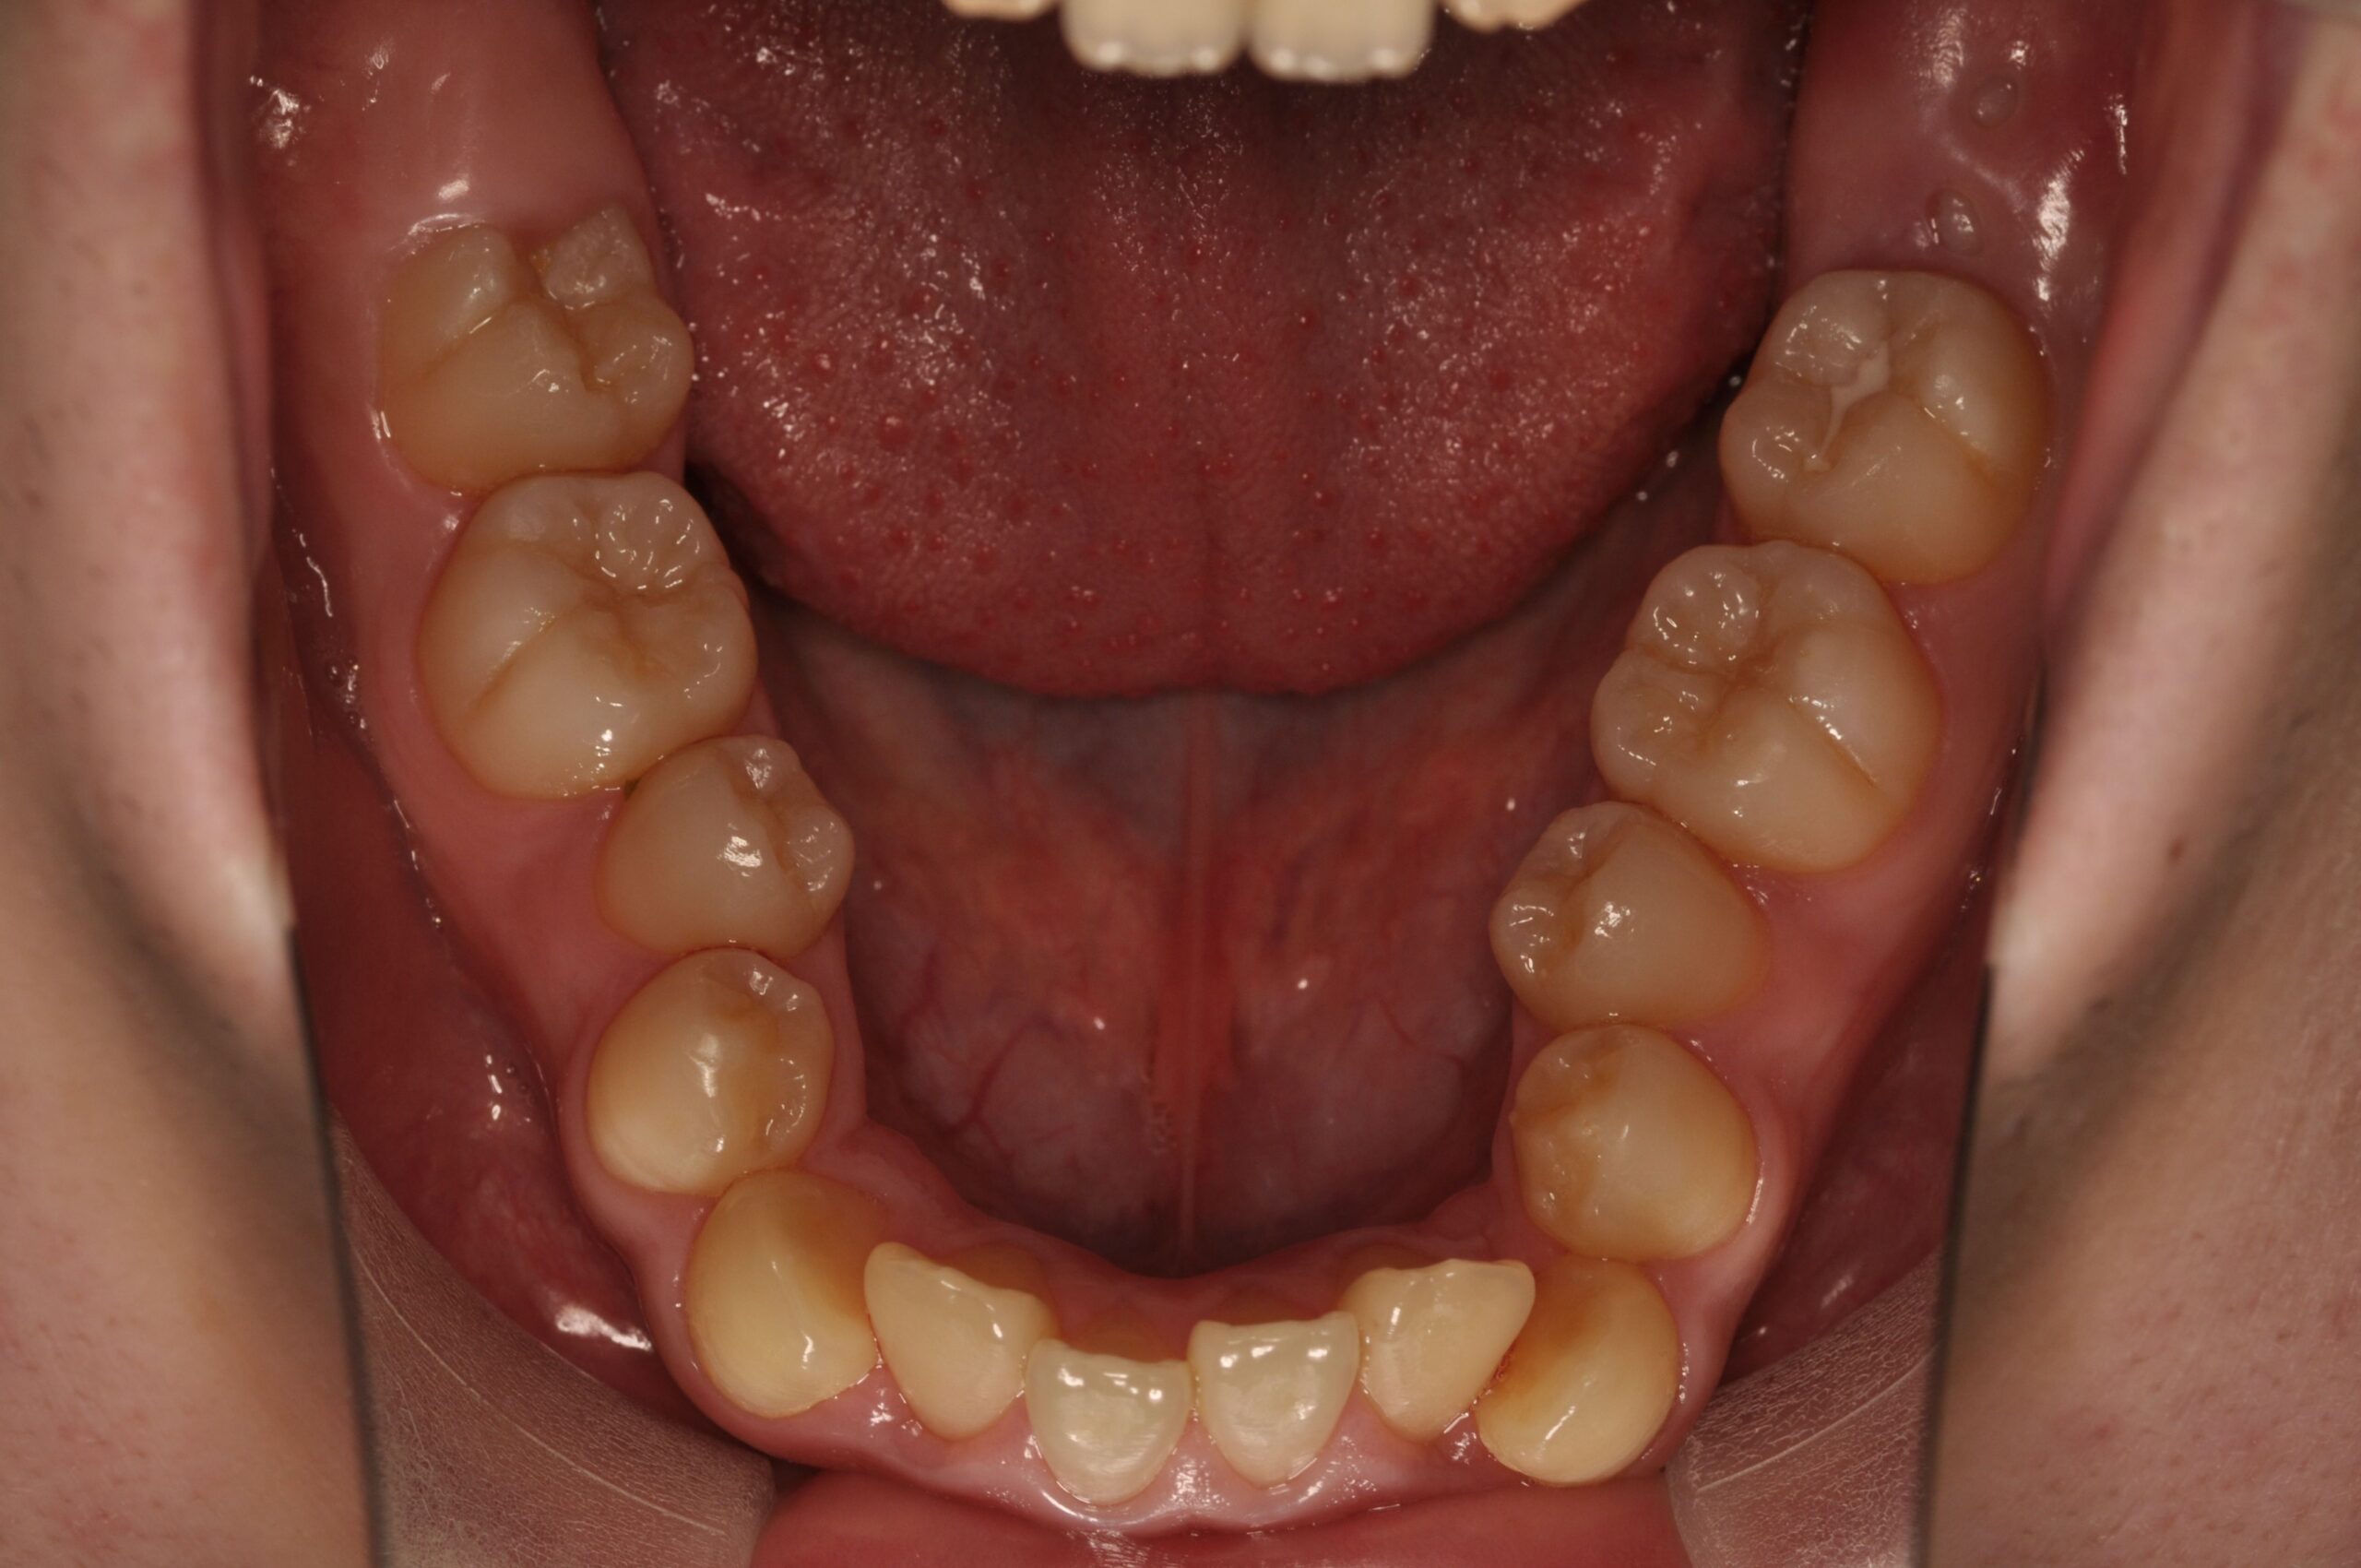

反対咬合(受け口、下顎前突) 叢生

Before

- 骨格性下顎前突症、下顎骨左偏位、叢生、 顎変形症として、外科的矯正術を計画。 叢生、右側第2大臼歯鋏状咬合。 上下顎第一小臼歯を抜歯し、抜歯空隙を利用し叢生を改善し、上下顎それぞれ歯列を整列し、矯正治療中に病院歯科口腔外科にて外科手術(近郊の病院歯科口腔外科にて、口の中から手術、2週間入院)により下顎骨の後退と左偏位の改善をし、適切なオーバージェット、オーバーバイトを付与する。